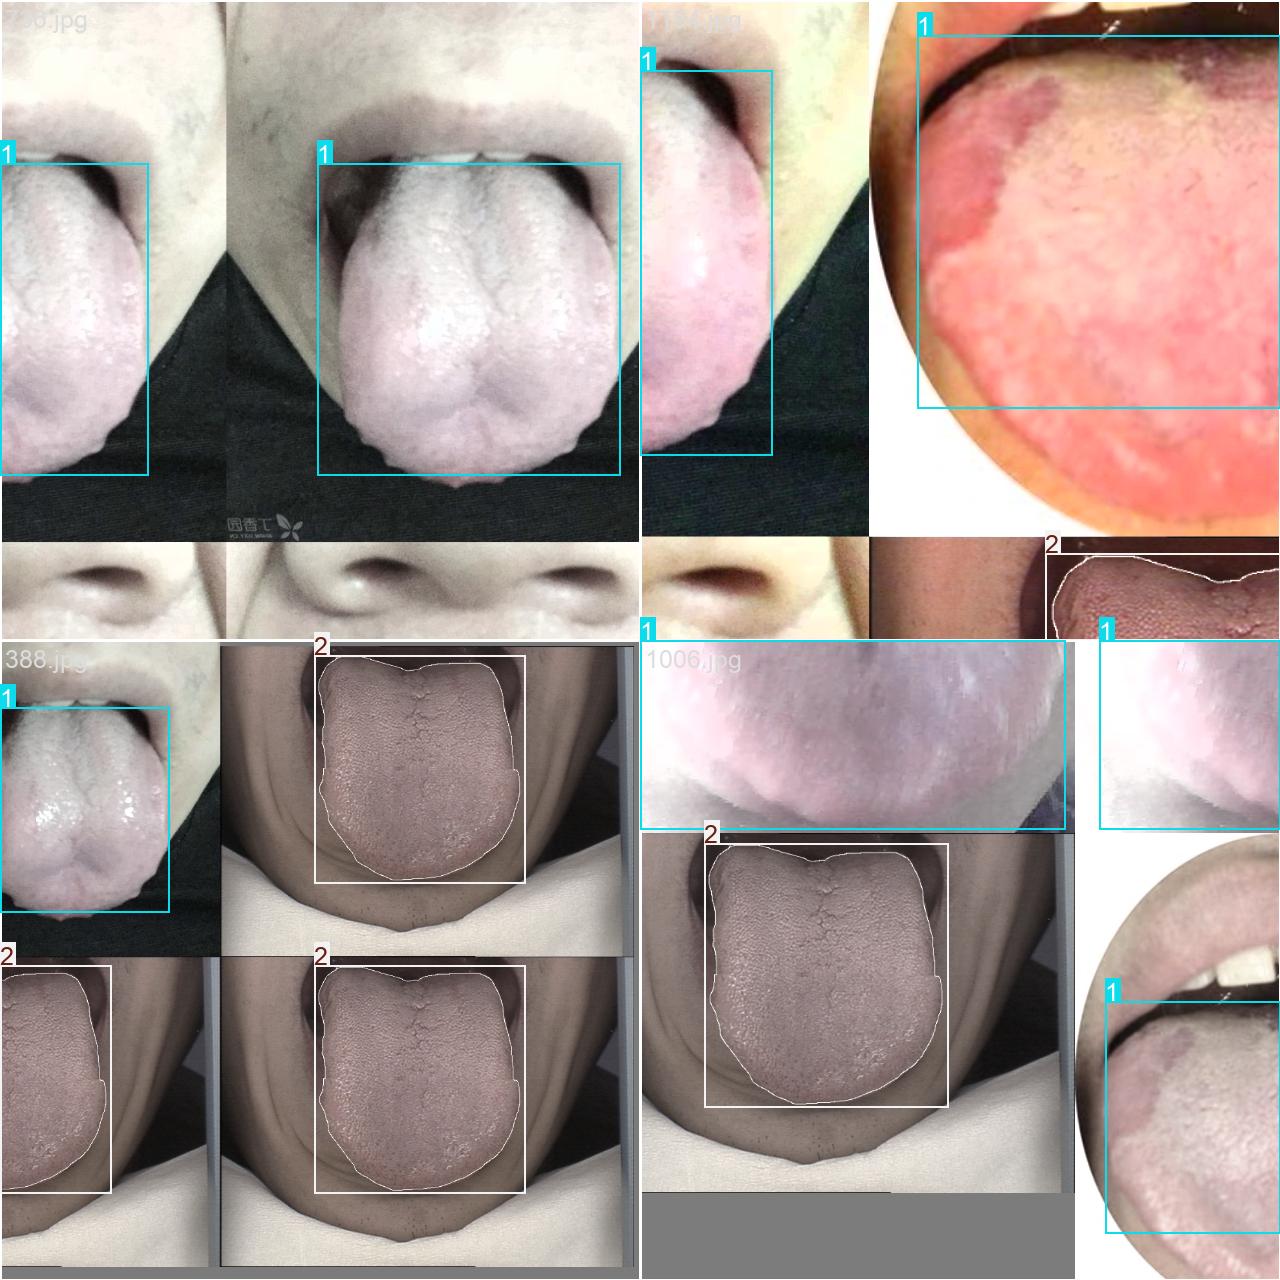

本研究使用了包含中医舌诊相关图像的数据集,并通过Labelimg标注工具对每张图像中的目标边框(Bounding Box)及其类别进行标注。然后主要基于YOLOv8n这种模型进行模型的训练,训练完成后对模型在验证集上的表现进行全面的性能评估及对比分析。模型训练和评估流程基本一致,包括:数据集准备、模型训练、模型评估。本次标注的目标类别为中医舌诊,数据集中共计包含1464张图像,其中训练集占1158张,验证集占306张。部分图像如下图所示:

部分标注如下图所示: